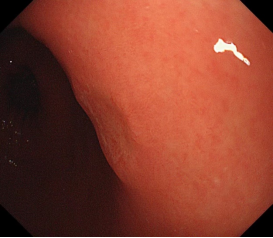

科室高清晰胃肠镜:正常的胃窦(线圈样腺管)和食管粘膜放大观察(IPCL)